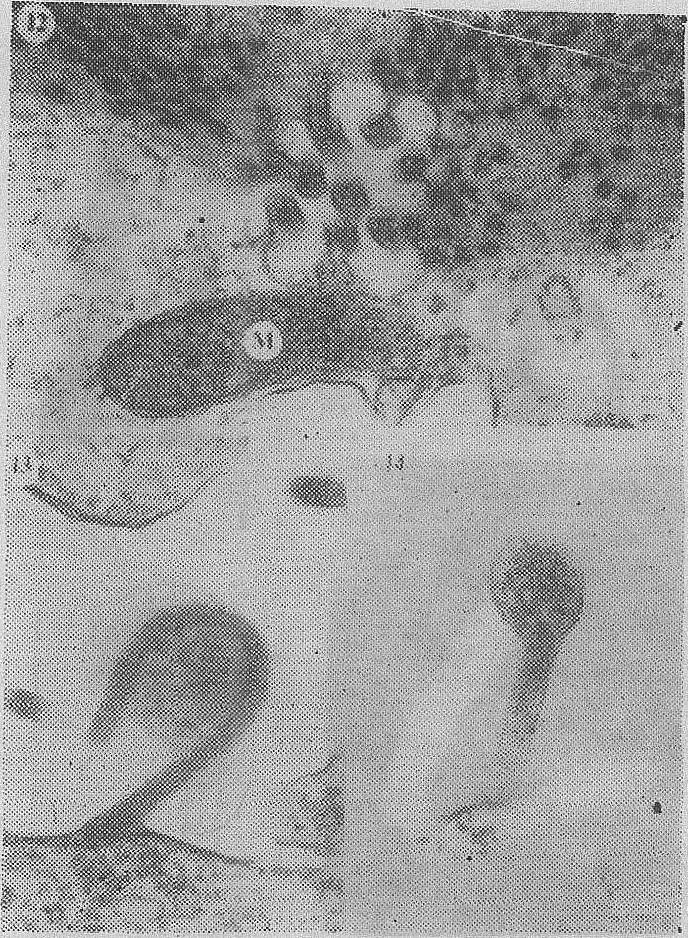

马尔堡和伊博拉两种病毒在形态上很相似,都呈多形性,在负染色的切片上,在电镜下,都表现为长管(鞭毛)状、U-字形、6-字形或圆形颗粒。(图1、2)。病毒颗粒含有一个内部螺旋状结构,可能就是核衣壳;一个单膜状胞膜和一个表面凸起层(图1、2)。颗粒直径约80nm,长度变化很大。1967年测量的马尔堡病毒,长度在130~2,600nm,中数为655nm,最长的达8000nm;1977年测量的伊博拉病毒颗粒,最长达14,000nm。病毒颗粒短小,呈“6”字形态和圆形,主要存在于病人或实验感染动物的组织和体液里,在细胞培养物中则多为畸形的颗粒,内含各样卷曲形状的核衣壳细丝,因而多为分岔的和较长的颗粒(图2、3、4)。

图1 马尔堡病毒(据Martini G.A d Siegest R)

图2 马尔堡病毒(据MartiniG. A d SiegestR)